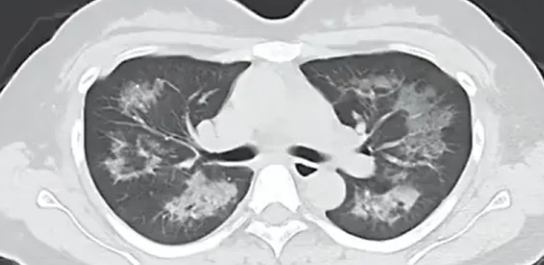

每天用2次定妆喷雾,22岁女主播肺里长满阴影!